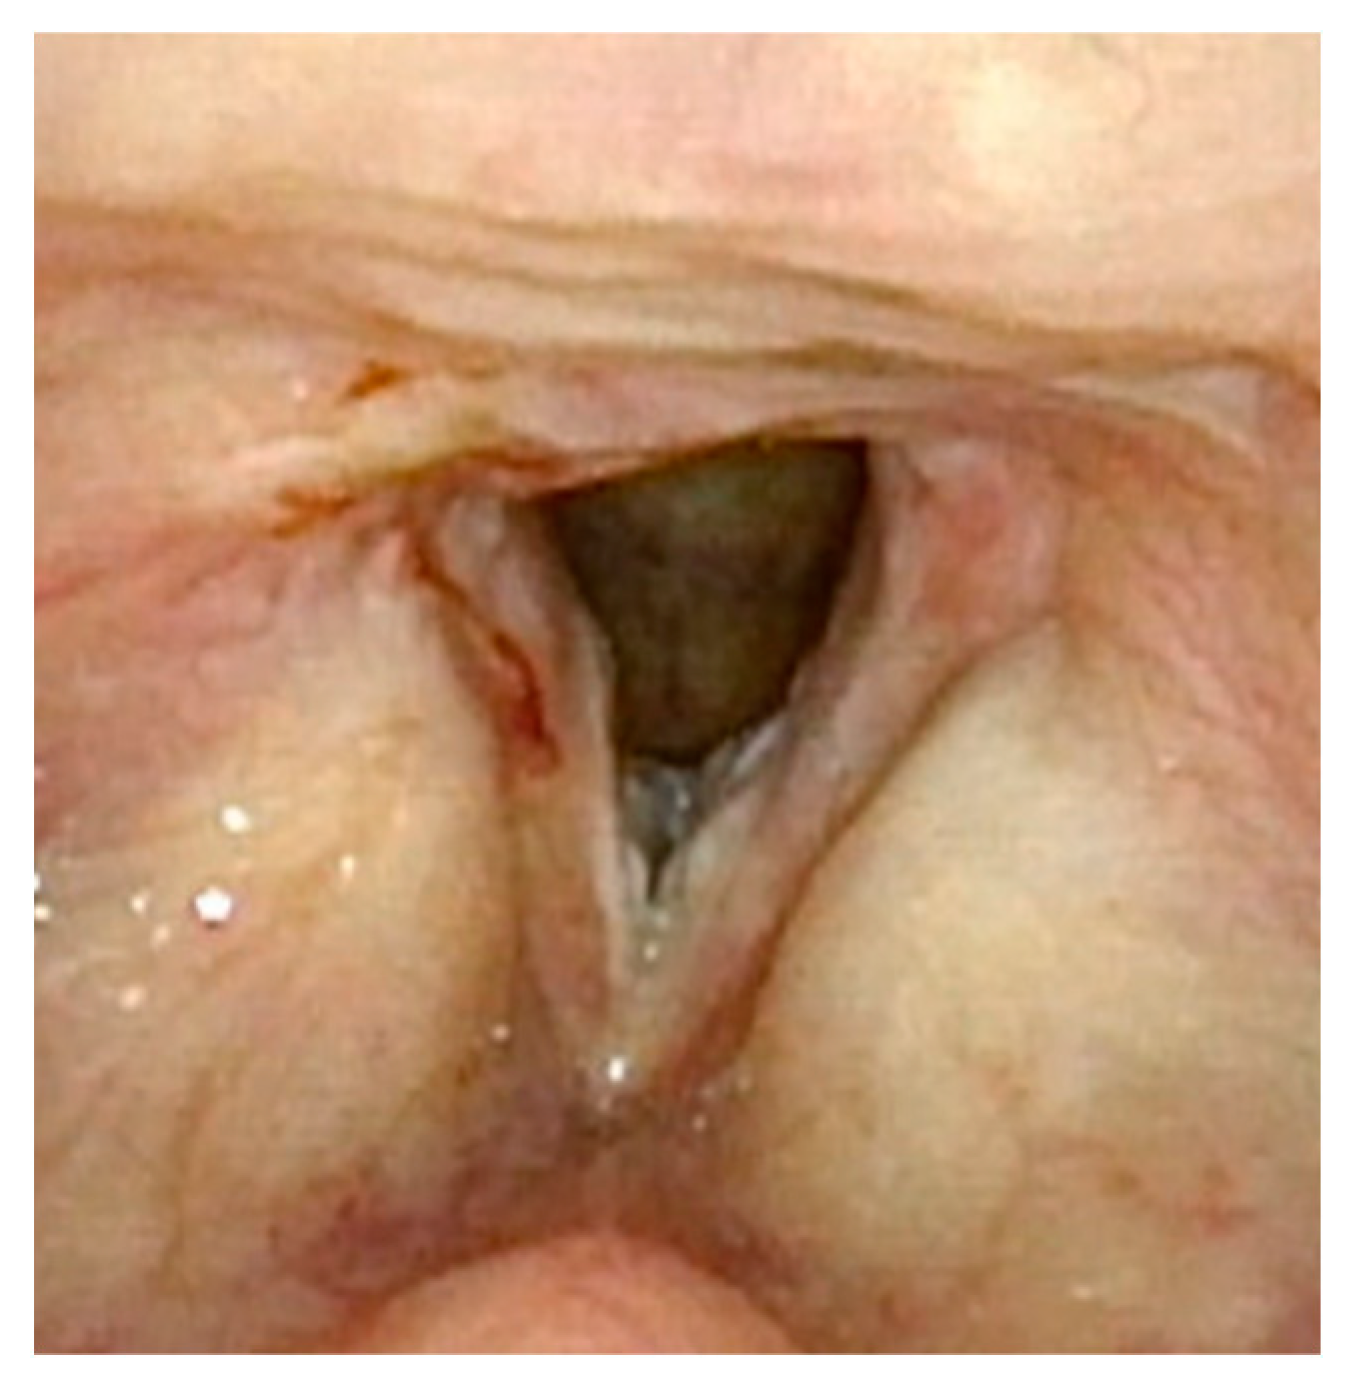

Figure 1 demonstrates a patient who had too aggressive anterior commissure laser treatment. A consequence of this was a very large anterior glottic web. Should this be encountered, the web may be lysed in the midline and steroid-injected (Figure 2). If the web is not the full thickness of the vocal folds, it should be cut with cold steel to help prevent the return of the web during healing. Once healed the web should be significantly improved (Figure 3). Consideration should be given to the dilation of the glottis following lysis.

Figure 2.

One week post-op following laser ablation of laryngeal papilloma and lysis of anterior glottic web.